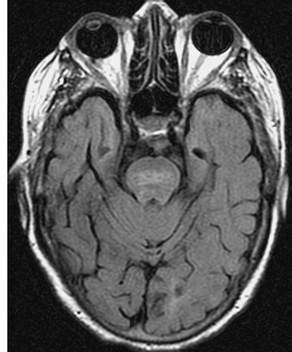

A pesar de la depuración de benzodiacepinas y litio (ahora a 0,01 mEq/L), la paciente no recuperó la conciencia por completo. Los EEG subsiguientes todavía mostraron una desaceleración theta generalizada y no se observaron más descargas epileptiformes. Asimismo, la repetición de la tomografía computarizada craneal no mostró nuevos hallazgos. Se realizó resonancia magnética por su mayor sensibilidad la cual mostro cambios de hipo hipodensidad en región del tallo (figura 1).

Figura 1. Resonancia magnética de la paciente que muestra cambios de desmielinizacion en tallo.